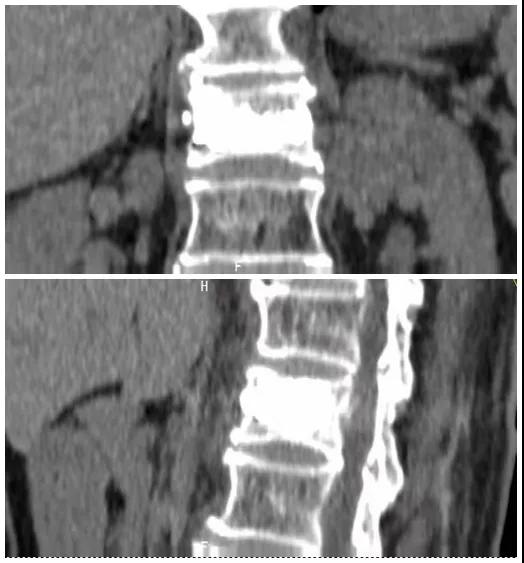

術(shù)后復(fù)查CT可見骨水泥彌散充分

經(jīng)術(shù)前分析詳細(xì)評估,由骨科副主任張宏宇及科室團(tuán)隊(duì)順利為患者進(jìn)行了經(jīng)皮穿刺椎體成形術(shù),術(shù)后患者疼痛明顯減輕。同時(shí),科室團(tuán)隊(duì)還為她制定了科學(xué)的抗骨質(zhì)疏松治療,目前患者已康復(fù)出院。